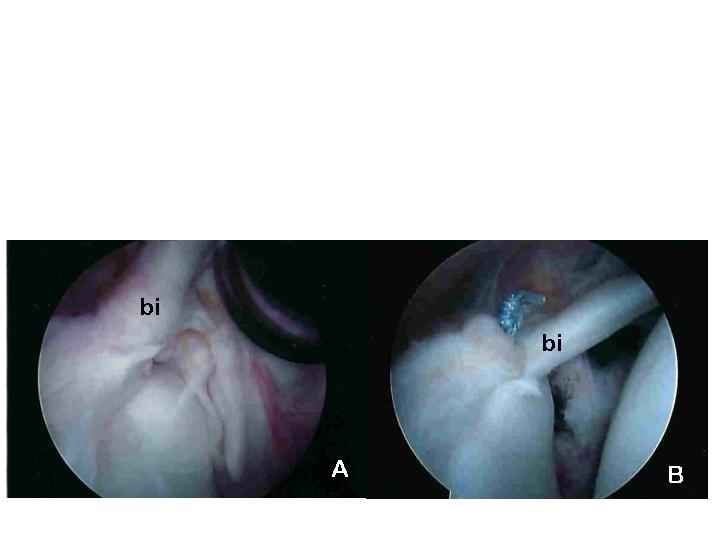

Other injuries, such as tears of the origin of the biceps muscle tendon (called a SLAP lesion) can also be seen and addressed during the procedure. Figure 8a shows the biceps (bi) and labrum torn away from the top of the glenoid. Figure 8b shows the biceps (bi) and labrum repaired to the labrum using a suture anchor.

Figure 8a & 8b